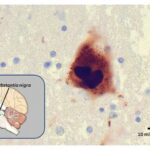

Per capire come funziona il vaccino e come reagisce il nostro corpo partiamo dalle metafore illustrate da Giuseppe Ippolito, Direttore scientifico dell’Ospedale Spallanzani che ha parlato dei “linfociti T” come maestri d’orchestra e degli anticorpi come soldati in prima linea. Il vaccino si chiama Grad-Cov2 utilizza come vettore un adenovirus (famiglia di virus a cui appartiene anche il raffreddore) dei gorilla. È stato sviluppato innestando il codice genetico della proteina spike del coronavirus su adenovirus (il vettore virale). Questo vettore è stato costruito in modo che non si replichi nell’organismo e non integri le informazioni genetiche che trasporta nel genoma umano.